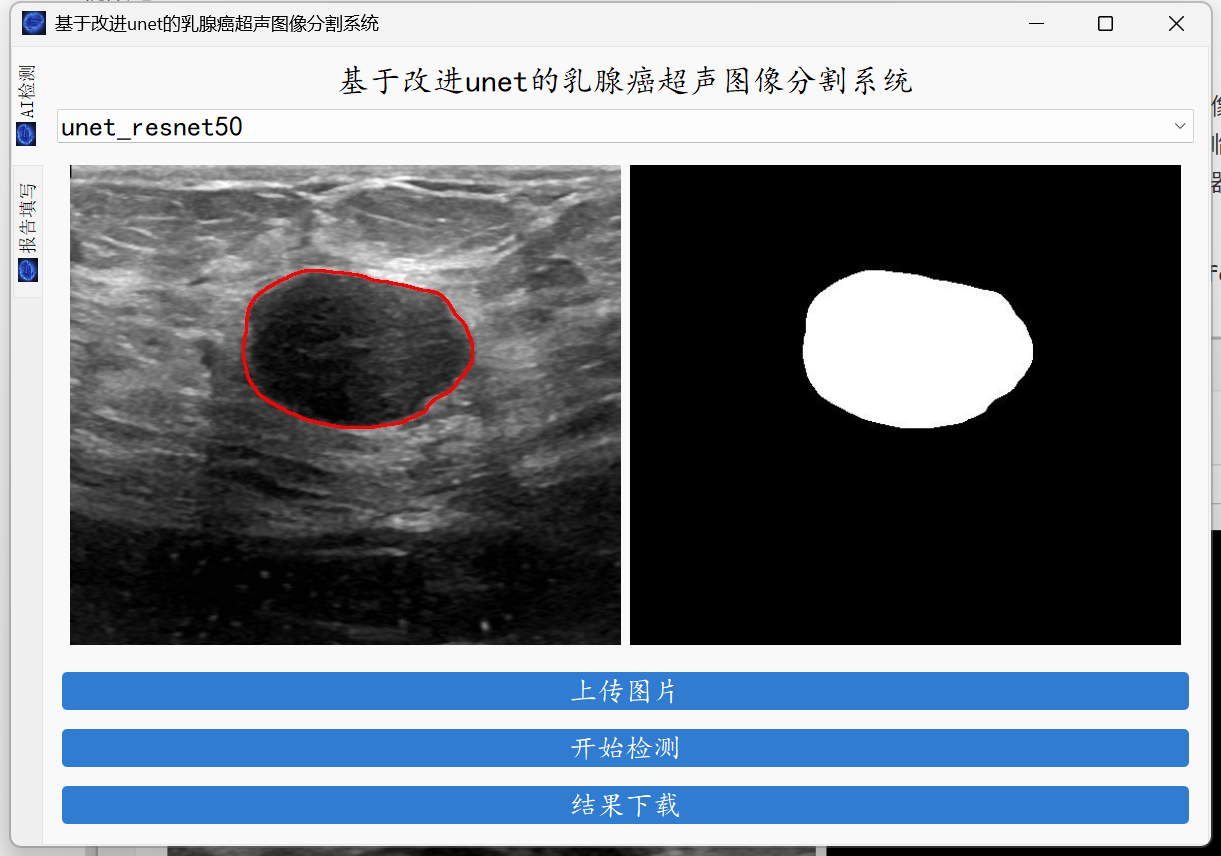

大家好,这里是肆十二!本次,我们为大家带来的是乳腺超神图像分割。深度学习技术的应用不仅提高了乳腺超神图像分割的精度和效率,也为医学影像分析带来了智能化的转变。借助人工智能,医生可以获得更多维度的辅助信息,从而做出更为精准的临床决策,推动了医学领域,尤其是在乳腺超神疾病的早期筛查、诊断和治疗方面的发展。在这期的教程中,我们将会教会大家如何使用服务器训练我们的乳腺超神图像分割模型以及将我们云端训练好的模型应用到本地的电脑上,最终实现的效果如下。

图形化界面封装

最后就是图形化界面的封装了,这里我们使用了pyqt的技术。

如果你是训练了自己的模型,请在下面的位置进行切换。

系统支持医学图像的分割、轮廓的查找以及简单的病例的记录。